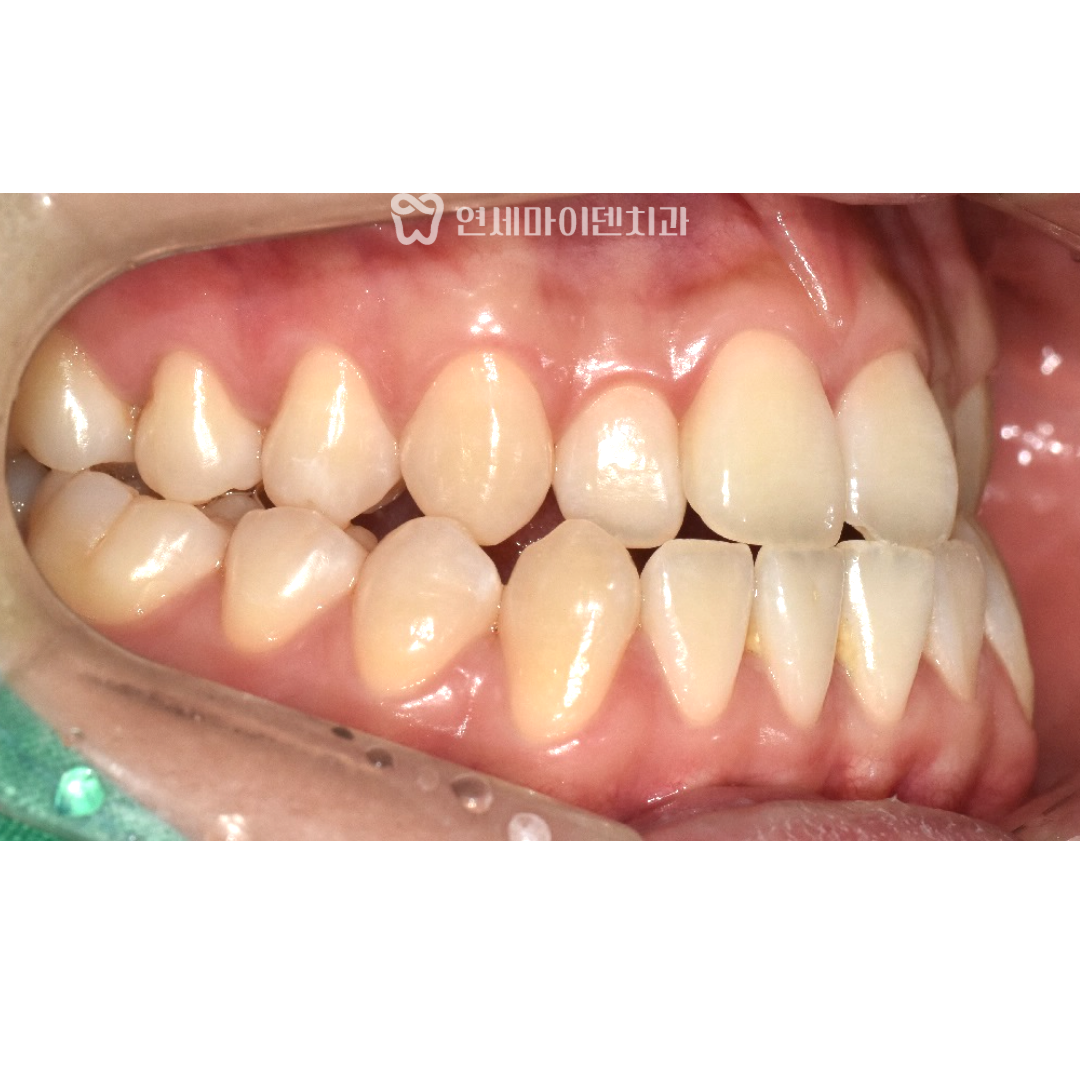

처음 내원하셨을 때 환자분의 치아 상태를 살펴보면

아래턱이 앞으로 나와있는 전형적인 3급 부정교합이 확인됩니다.

흔히 말하는 주걱턱 상태이며, 위아래 치아까지 반대로 맞물려 있었습니다.

위턱은 좁고 아래턱은 상대적으로 발달해서

치아 배열 자체가 많이 어긋나있는 상황이었습니다.

특히 윗니는 앞으로 튀어나와있고

아랫니도 안쪽으로 기울어져 있는 모습을 확인할 수 있습니다.

이런 상태는 교합 불균형을 유발해서

장기적으로 치아 건강에도 영향을 미칠 수 있습니다.